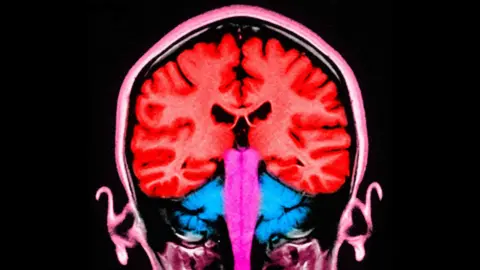

Brain stimulating test makes people 'less selfish'

Scientists have discovered how to make people less selfish - at least temporarily - by stimulating two areas of their brain. In a new study carried out at the University of Zurich, 44 volunteers were asked to decide how to split an amount of money between themselves and an anonymous partner. During the experiment, an electrical current was applied to the frontal and parietal areas of the brain - situated at the front and towards the back. When these areas were stimulated at the same time, the participants gave away more money. "The effects were not huge, but they're consistent," said Prof Christian Ruff, one of the lead authors who carried out the experiments. "Statistically, we really see an increase in their willingness to pay." As well as revealing something about the mechanisms behind fundamental human behaviour, the findings, researchers say, could be useful in treating some brain disorders. "There are people who have profound problems with social behaviour, because they can't take other people's perspective into account and are constantly behaving selfishly," Prof Ruff told BBC Radio 4's Inside Science. "That's when we could use this." In the case of this experiment, the effects were short-lived. "To really change behaviour in the longer term, you would have to do it repeatedly," said Prof Ruff. He compared the potential effects to going to the gym. One workout will not improve your fitness, "but if you go to the gym twice weekly for a period of two months, your body changes. This is the same." This new discovery, published in the journal PLoS Biology, builds on their previous study, which monitored brain activity while participants played the same money-sharing game. In that study, the researchers pinpointed the two brain areas that appeared to be "talking to each other" - with brain cells firing at the same frequency - when players gave away more money. Those two brain areas are known to play a role in decision-making and in empathy, or distinguishing the feelings of others from our own. When a more selfless decision was made, the empathy region and the decision region appeared to communicate. So for this study, the researchers wanted to find out if they could use electrical stimulation to "nudge" people towards more selfless decisions. One anonymous volunteer, who tried out the brain stimulation test, said the experience felt "like a warm shower or small drops of rain" on the scalp. "Immediately after starting the stimulation, I was making the decisions displayed on a screen. At no time did I have the sensation that the stimulation was impacting my decisions." Identifying this selfless decision brain activity, in multiple people, strongly suggests that altruism is hardwired in our brains; that it evolved to make us take care of others. Being able to influence and change that mechanism, Prof Ruff explained, "is what makes this discovery clinically relevant". Prof Ruff's co-author, Dr Jie Hu from East China Normal University, said: "What's new here is evidence of cause and effect. "When we altered communication in a specific brain network using targeted, non-invasive stimulation, people's sharing decisions changed - shifting how they balanced their own interests against others." But should we be concerned - or unsettled - by an experiment that influences behaviour in this way? Prof Ruff says "absolutely not". "This is medically regulated specifically for these experiments," he explained. "It goes through an ethics committee and people give informed consent, which they can withdraw at any time. The neuroscientist compared that to the influences on our behaviour from social media and advertising. "There you have no control over what you're exposed to [and how your brain responds to it]," he said. From helping people cope with age-related disorders to altering our perception of physical pain, music's impact on our bodies can ring loud. Eating fibre can improve health, lengthen lifespans, and even protect our brains. Yet many of us are still coming up short on this "essential nutrient". Megan Jackson says baking is her "coping mechanism" after an inoperable brain condition diagnosis. Sometimes dubbed the 'pleasure chemical', dopamine is often wildly misunderstood. Nikolay Kukushkin delves into what the much-discussed neurotransmitter really does to our brains. Our eyes can frequently play tricks on us, but scientists have discovered that some artificial intelligence can fall for the same illusions.